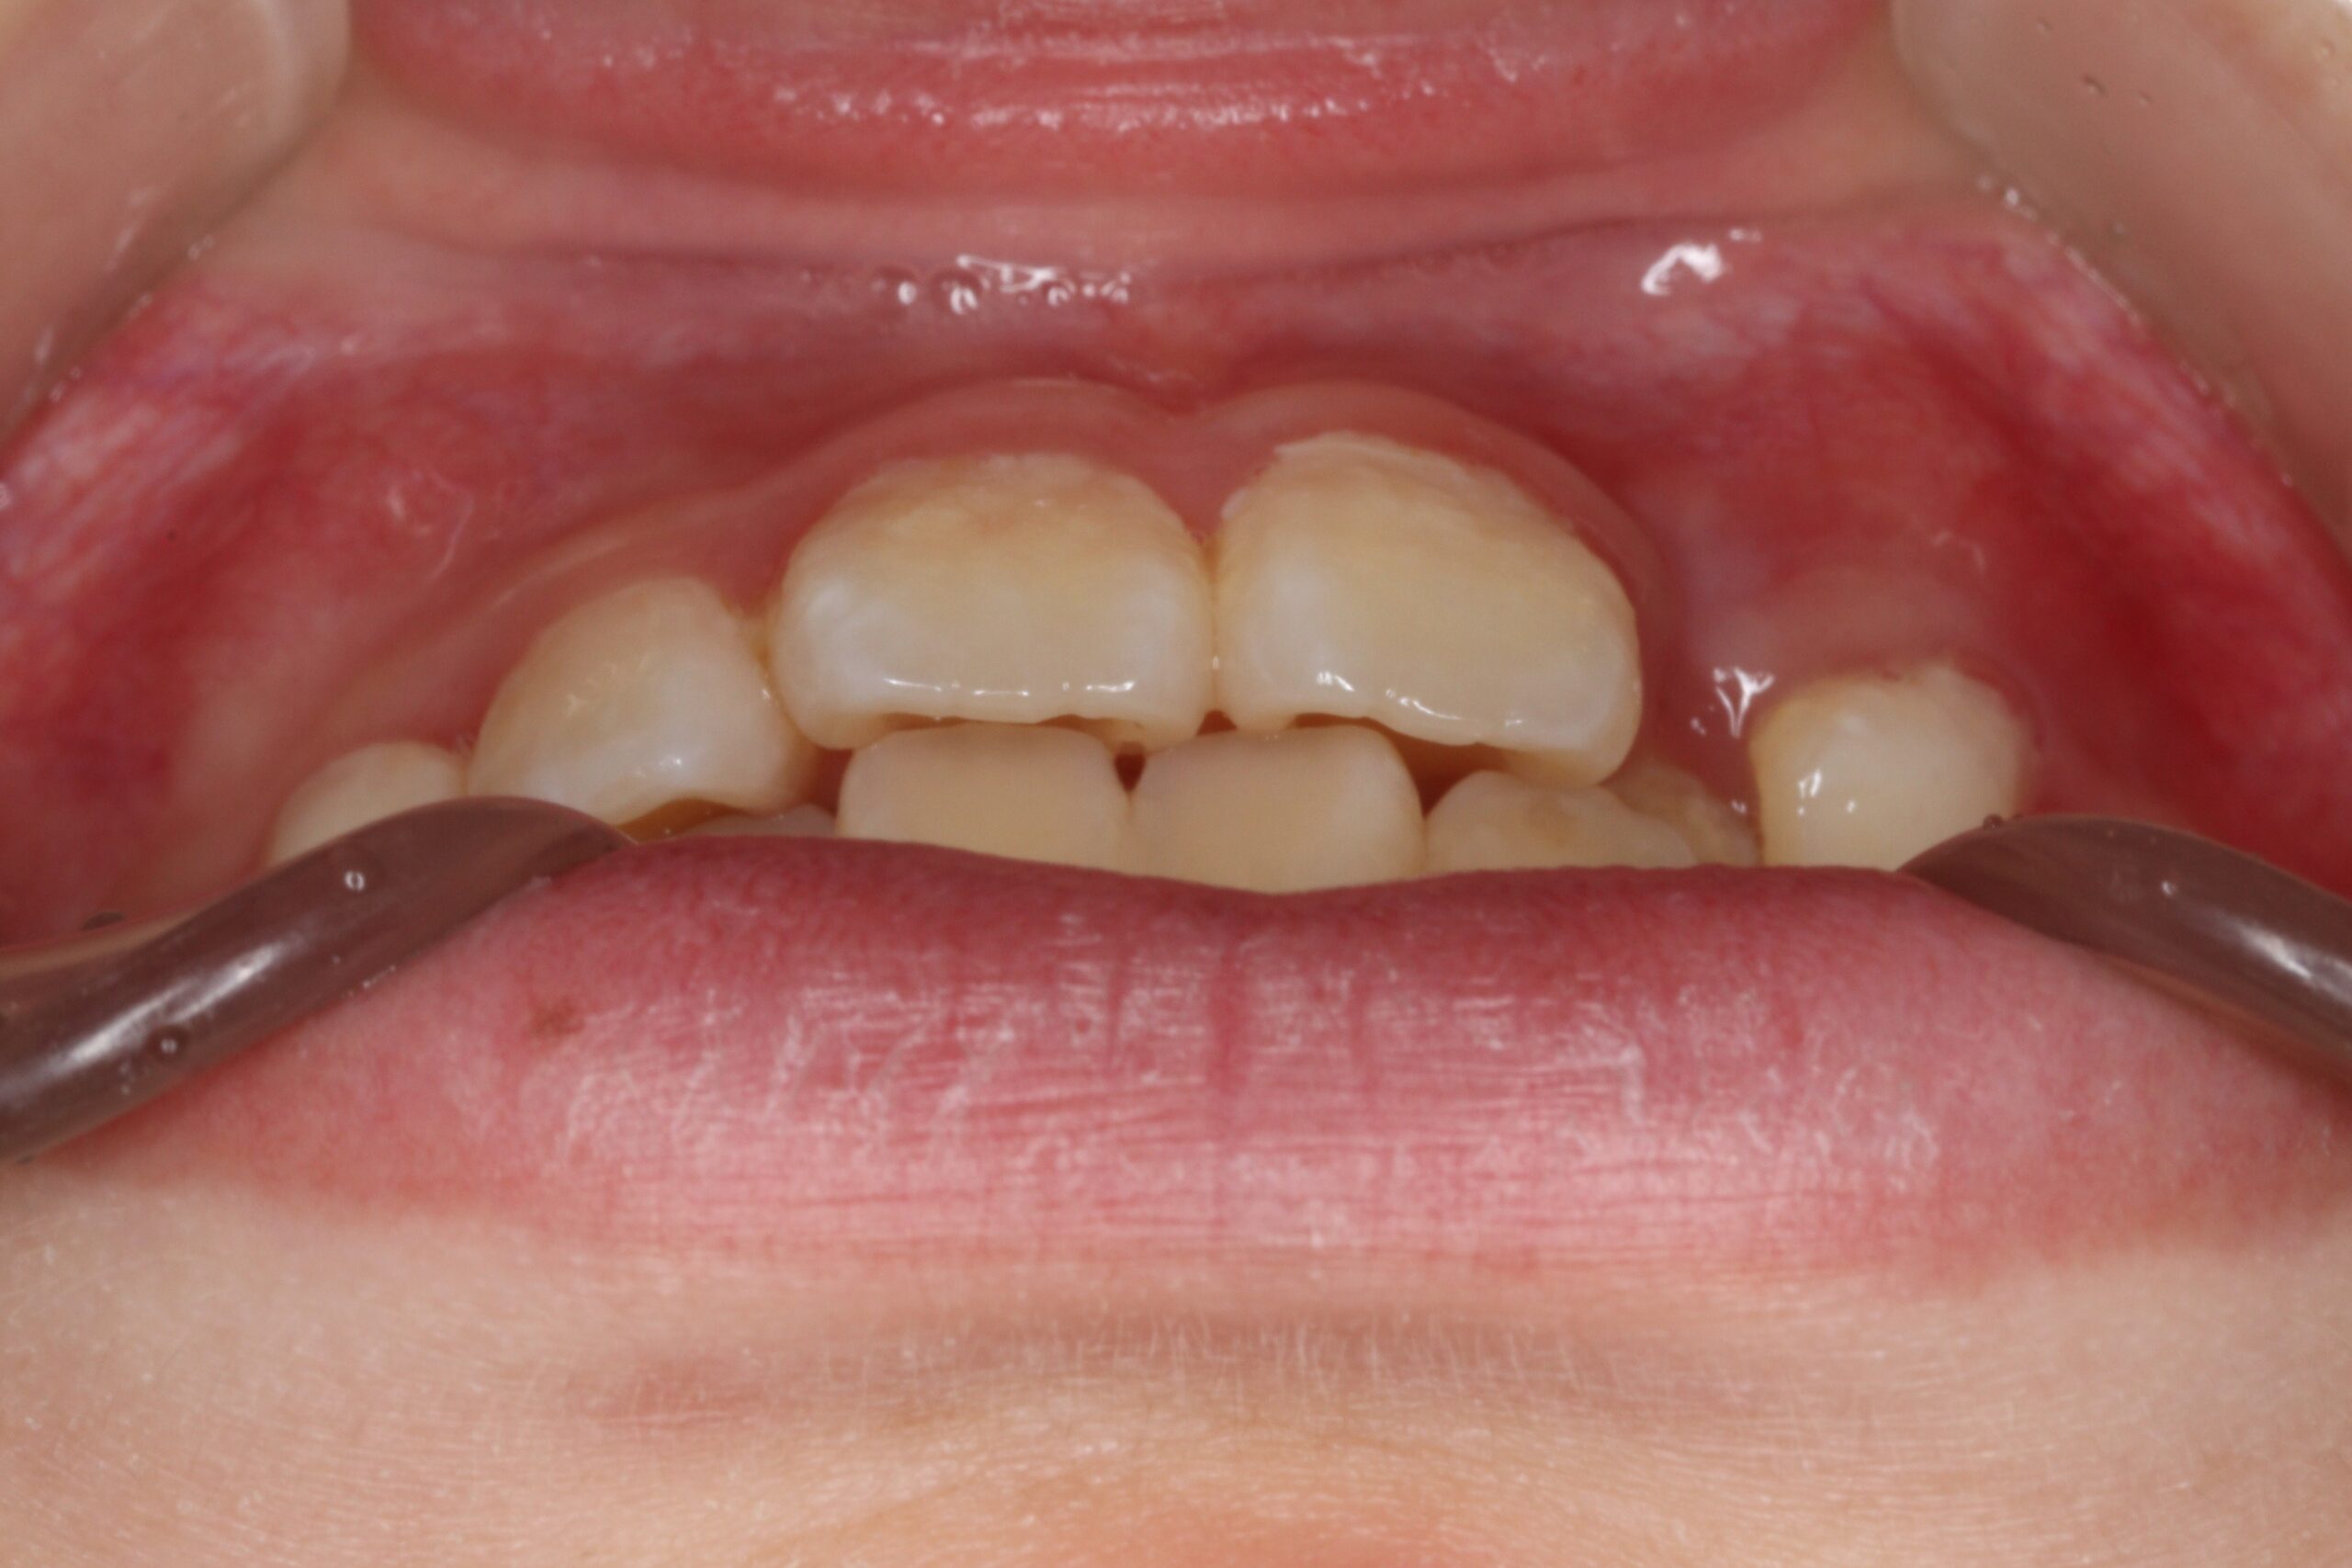

矯正術前:前歯部あおり

矯正術後:前歯部あおり